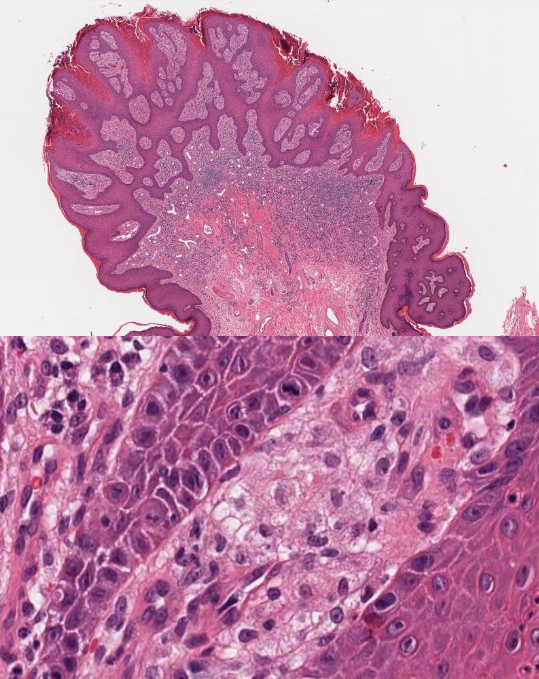

Tricholemmoma

Verruciform Xanthoma